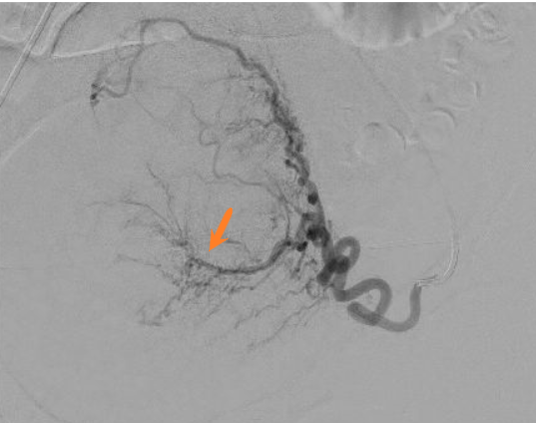

Image d'artériographie d'une procédure d'embolisation utérine du côté droit et gauche chez une même patiente.

Les formations tubulées noires correspondants aux artères et vaisseaux sanguins telles que visualisées par le radiologue interventionnel lors de l'injection de produit de contraste.

On individualise successivement le cathéter permettant l'injection du produit (flèche noire), l'artère utérine (flèche rouge) avec visualisation d'un des fibromes utérines à traiter chez cette patiente (flèche orange) sous forme d'un réseau artériel en arc de cercle.